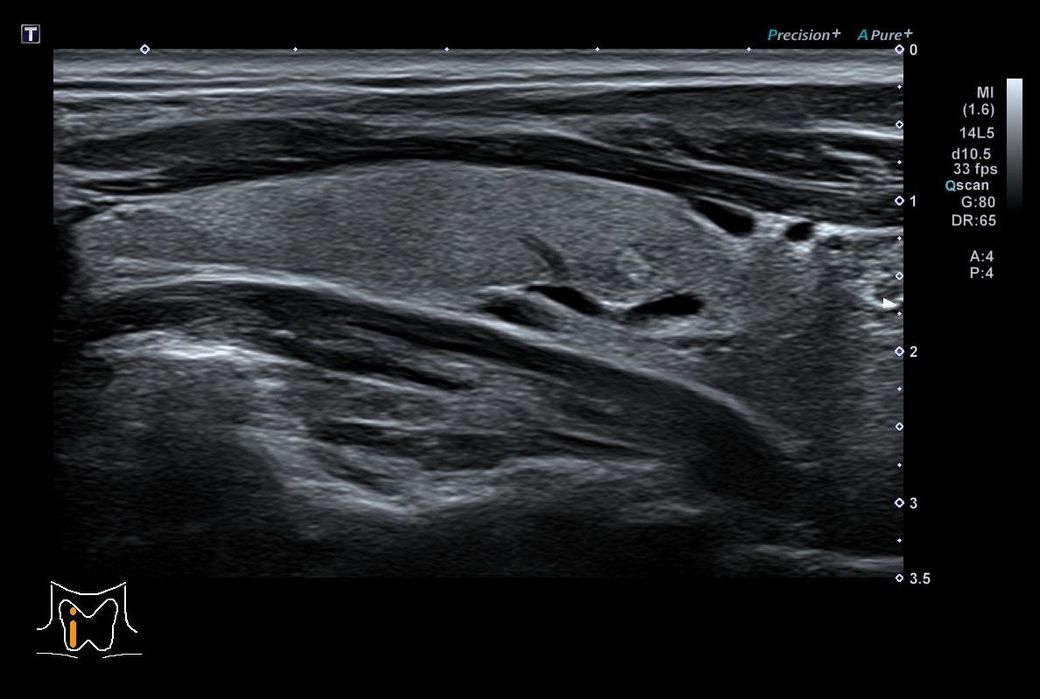

갑상선 초음파인데 모양이나 위치가 안좋나요?

건강검진을 했는데 갑성선 우엽에 0.5cm 석회포함결절 이라고 하는데

위치나 상태가 안좋은 편일지요?

• 1번 째 사진